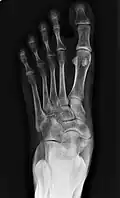

-

Cornuate navicular bone -